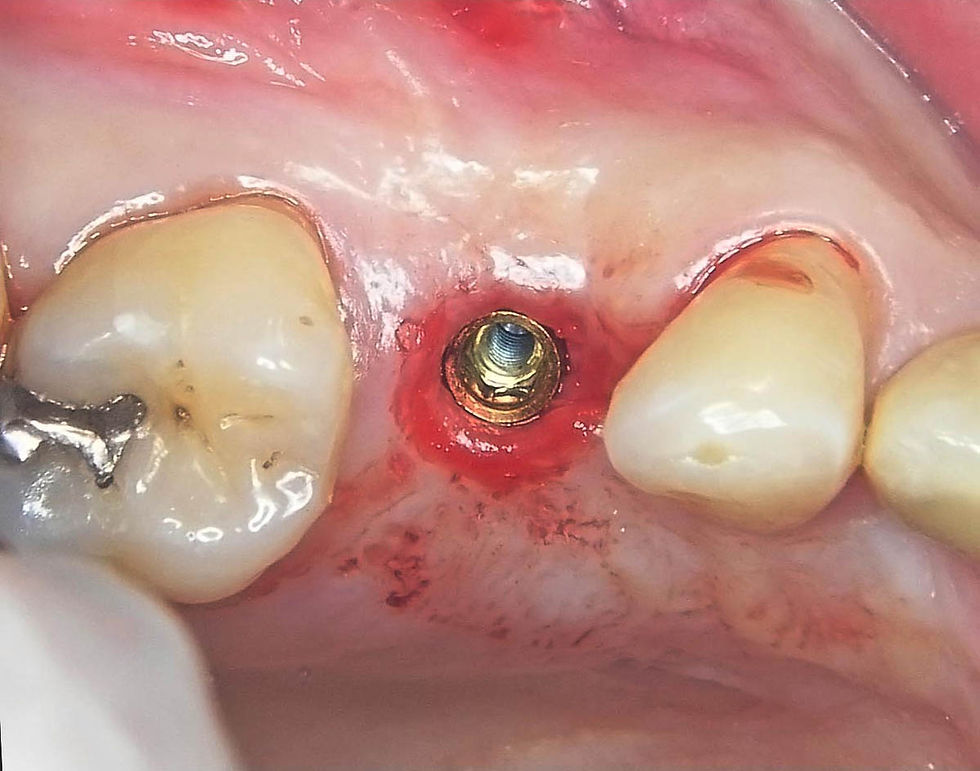

Insertion of the implant using the Easy Insert driver, which guarantees the preservation of the implant connection.

Insertion of the implant using the Easy Insert driver, which guarantees the preservation of the implant connection. GO TO THE VIDEO